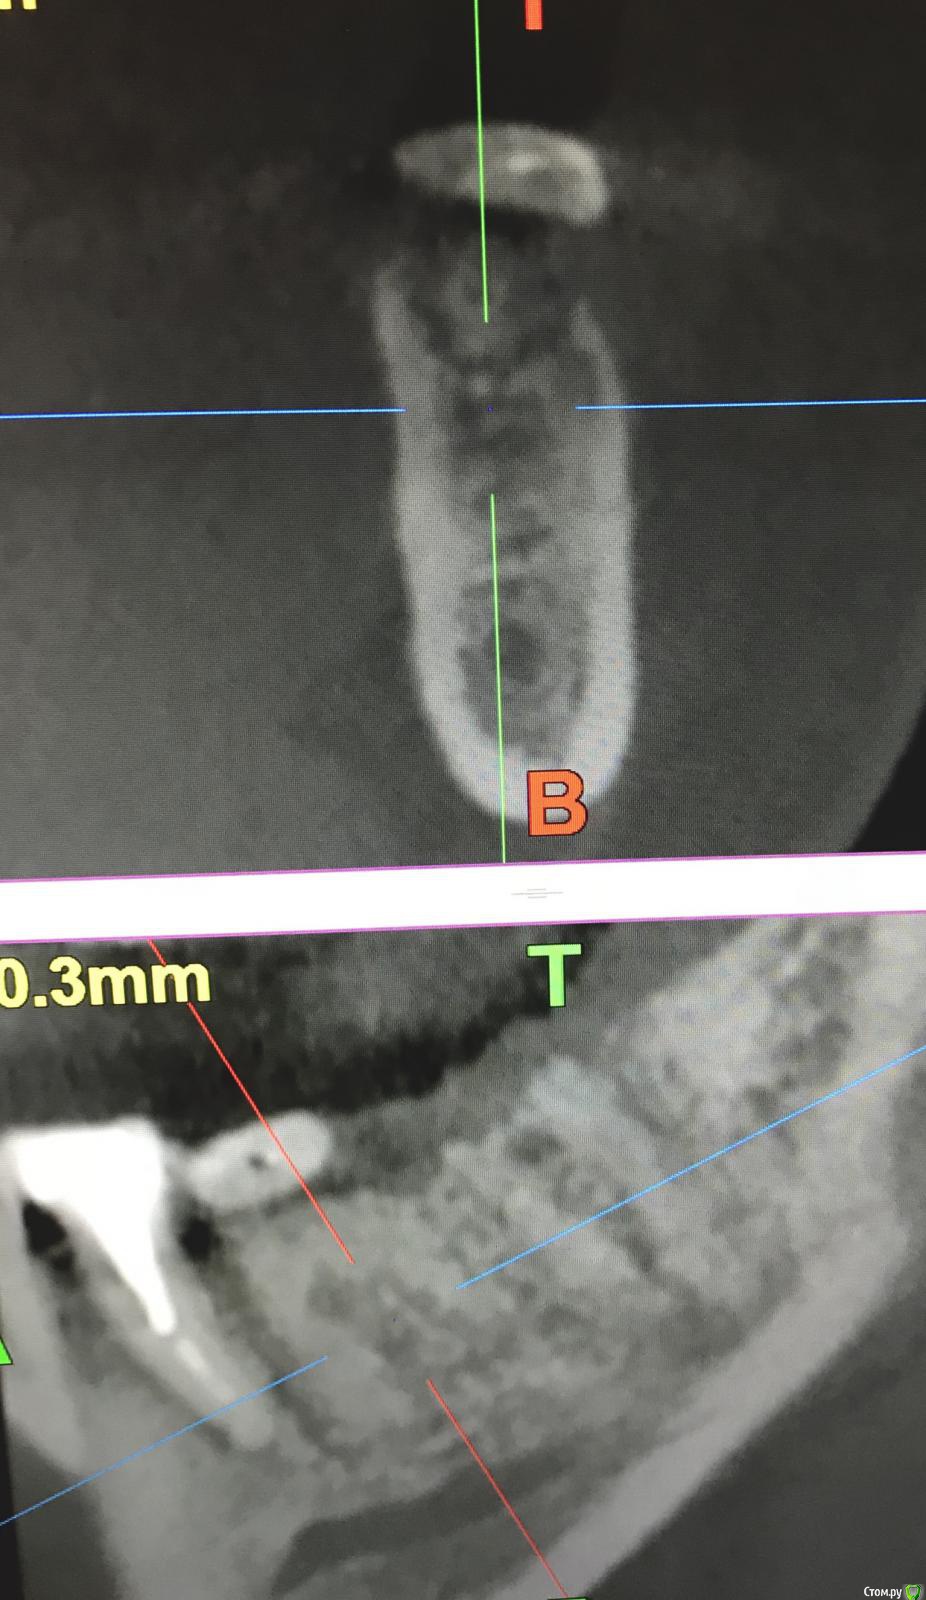

annda Опубликовано 7 августа, 2018 Поделиться Опубликовано 7 августа, 2018 (изменено) Тоже попробовала.Застарелый перелом корня.Два свища на момент приема.Удаление всего,спилила на коронковом фрагменте до связки,канал закрыла IRMом,в дефект порошок Лилпласт на АPRF ,обратно фрагмент притопила,фиксация на ретейнер.Снимок через две недели.Теперь думаю,не длинноват ли фрагмент.Хотя,может и проекция снимка вводит в заблуждение.КТ срезы сняла с экрана,пардон за качество. Изменено 7 августа, 2018 пользователем annda 3 Ссылка на комментарий

Bier Опубликовано 7 августа, 2018 Автор Поделиться Опубликовано 7 августа, 2018 ну вроде как длинный фрагмент даже лучше. Советую через 2-3 мес вытянуть его ортодонтически и только потом удалить. Ссылка на комментарий

annda Опубликовано 8 августа, 2018 Поделиться Опубликовано 8 августа, 2018 (изменено) Ортодонтически—может просто ретейнер переклеить?Он не обожжен... Изменено 8 августа, 2018 пользователем annda Ссылка на комментарий